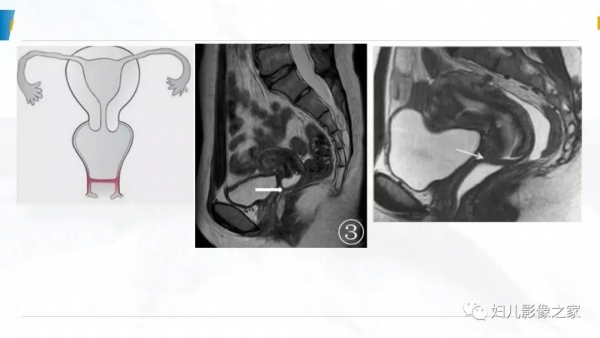

阴道积血诊断及鉴别诊断

女,10岁,以“间断下腹痛7天”为主诉入院。入院查体:生命体征平稳, 心肺听诊无异常,腹软,肝脾未及,余无明显异常。

专科检查:外阴发育尚可,处女膜开口较小,棉签探入约4cm,无膨 隆,肛诊:子宫、宫颈膨隆,最低处距处女膜约4cm。

辅助检查:彩超(县中医院,2021-10-08):子宫体积增大,子 宫肌层变薄,内膜线消失,宫腔扩张,子宫颈管扩张,内充满大量液 性暗区,呈密集点状,阴道未见明显扩张。提示:1.胆囊内强回声2.胆 囊壁毛糙3.考虑处女膜闭锁。